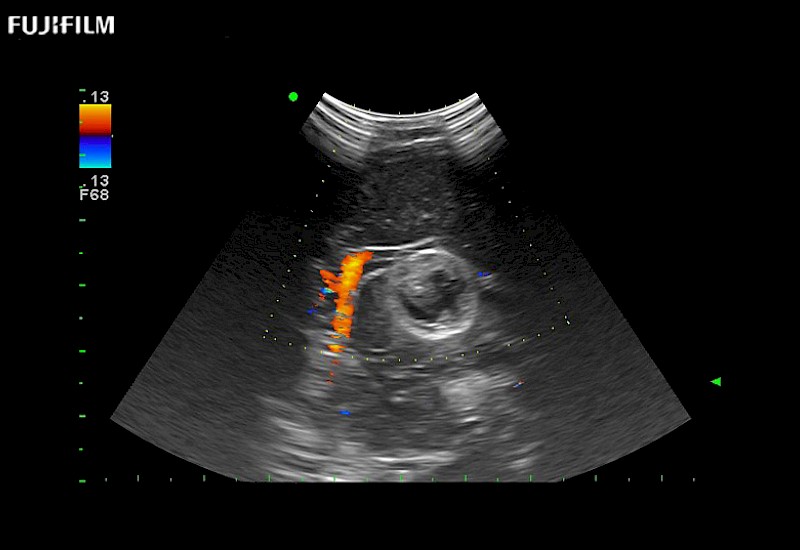

Extraordinary high-resolution digital imaging

Exceptional transducers

for use during: Cranial guidance, Burr-Hole guidance, Spinal Cord guidance, Pituitary guidance, Micro-Surgery guidance

Multi-Parametric imaging modalities